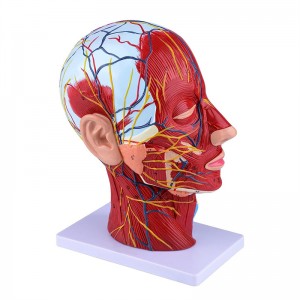

| Awọn ẹya | Awoṣe naa fihan ọrọ ayọ ti agbegbe ti apakan ti inu ati ọrun, ati awọn ẹya ara ti awọn iṣan ara ati awọn ẹya ara, ati awọn ẹya 84 wa ti o nfihan awọn ami lapapọ. |

Ni 1: 1 LIGESED】 Mediani Akan Media ti 1: 1 ori nla ti o tobi julọ & ade nla ti iṣan iṣan ti iṣan ti o ni iṣan iṣan. Iṣẹ adaṣe daradara. Nfunni ni kikun ti awọn ẹya anatomical.

Awoṣe iṣan iṣan】 alaye ti o ga pupọ, awọn nọmba ti samisi, jinlẹ ti awọn iṣan to loye awọn iṣan ati ọrun inu & ọrùn ti ori & ọrun. Atter-mq-iṣọn, buluu-vening, alawọ ofeefee.

Awọn ẹya】 o ṣafihan awọn iṣan ti o fara ara ti oju ti o farabalẹ; Awọn ohun elo ẹjẹ ti o dara julọ & awọn iṣan ti oju & scalp; Awọn ẹya inu ti Patiod erumlandi ati oke atẹgun; Eto apakan-ilẹ Sagittal artical ti ọpa ẹhin.

Awoṣe yii fihan awọn alaye ti ọrun-ọrun ati apakan sagittital ti eniyan. pẹlu superficial

awọn iṣan ti oju oju; Awọn ohun elo ẹjẹ ti o ga julọ ati awọn iṣan oju ti oju ati awọsanma; Awọn ẹya inu

ti parotid blandi ati atẹgun oke; Eto apakan-ilẹ Sagittal artical ti ọpa ẹhin.

Awoṣe ṣe afihan ọrọ-ọrọ ti agbegbe ti aarin ati awọn apakan sagittal ita ti ori ati ọrun ati awọn ẹya ara ati awọn ẹya ara ẹrọ ti ofura, pẹlu apapọ awọn olufihan oju opo wẹẹbu 100.

Awoṣe yii jẹ ori ti o tobi pupọ ati awoṣe iṣan ti o ni agbara nla ati eto aarin ti ẹṣẹ parotid ati atẹgun oke, ati apakan apakan apakan Sagitttal ti ọpa ẹhin